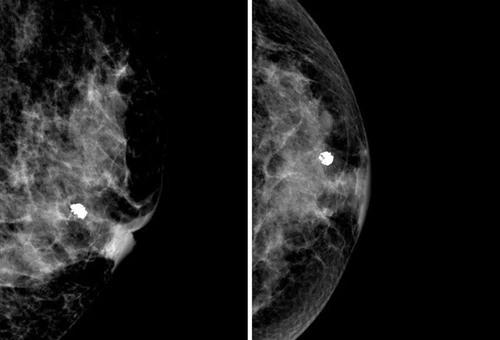

乳房的鈣化點(diǎn)大部分都是良性的,或伴有其他良性病變,如乳腺增生。所以,乳房鉬靶上如果看到大大的白點(diǎn),通常就是良性鈣化點(diǎn),如纖維腺瘤就常常會在鉬靶的影像上出現(xiàn)爆米花狀的粗糙大白點(diǎn)。

2.惡性鈣化

當(dāng)癌細(xì)胞不受控制地生長,這一群癌組織會變得很擁擠,導(dǎo)致里面小部分的細(xì)胞會因組織缺氧而壞死。這時(shí),我們身體無法清除壞死的組織,這些細(xì)胞就變硬而形成鈣化點(diǎn)。

因此,惡性鈣化點(diǎn)的特點(diǎn)是:聚集很緊密,簇聚于局部區(qū)塊,且鈣化點(diǎn)很小,形狀不規(guī)則,每個(gè)點(diǎn)都不太一樣,或有針尖狀、小桿狀、分叉狀、簇狀及泥沙樣多屬于惡性病變。